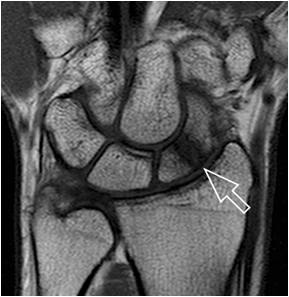

Fig. 7. Patent with suspected scaphoid fracture. The wrist film and the scapoid series did not show a definite fracture line. A faint line is seen in the proximal third of the scaphoid. MR imaging of the wrist reveals a bone marrow edema and fracture indicated by a low signal area on a T1 weighted image.